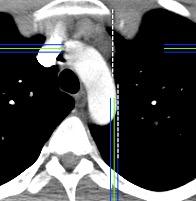

Tráquea en sable

Estrechamiento en plano coronal con diámetro normal en el sagital

60 pacientes con EPOC.

97% tráquea en sable.

Greene R et al: “Saber-sheath” trachea: a clinical and functional study of marked coronal narrowing of the intrathoracic trachea. Radiology 1975

También en asociación con

Lipomatosis mediastínica.